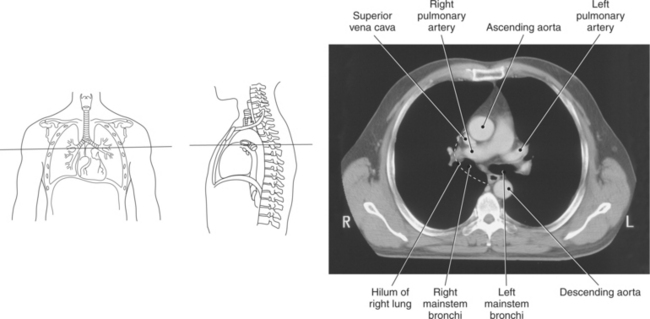

Blood travels to and from the heart through the great vessels, which include the aorta, pulmonary arteries and veins, and superior and inferior venae cavae (Figures 6.54 and 6.55). The aorta is the largest artery of the body and can be divided into the ascending aorta, aortic arch, and descending aorta. The ascending aorta begins at the base of the left ventricle at the level of the sternal angle, then curves superiorly and posteriorly as the aortic arch over the root of the left lung. The top of the aortic arch is approximately at T3 (Figures 6.56 and 6.57). The arch continues as the descending aorta posterior to the left bronchus and pulmonary trunk, on the left side of the vertebral body of T4 (Figures 6.58 and 6.59). The descending aorta passes slightly anterior and to the left of the vertebral column as it descends through the thoracic and abdominal cavities (Figure 6.60). While in the thoracic cavity, the descending aorta is commonly called the thoracic aorta, and while in the abdominal cavity, it is called the abdominal aorta. The pulmonary trunk is the origin of the right and left pulmonary arteries and lies entirely within the pericardial sac. It arises from the right ventricle and ascends in front of the ascending aorta, courses posteriorly and to the left, where it bifurcates at the level of the sternal angle (T4) into the right and left pulmonary arteries (Figures 6.61 through 6.63). The pulmonary trunk is attached to the aortic arch by a fibrous cord called the ligamentum arteriosum, the remnant of an important fetal blood vessel (ductus arteriosus) that links the pulmonary and systemic circuits during fetal development (Figures 6.54 and 6.61). The right pulmonary artery courses laterally, posterior to the ascending aorta and superior vena cava, and anterior to the esophagus and right mainstem bronchus, to the hilum of the right lung. At the root of the right lung, the right pulmonary artery divides into two branches, with the lower branch supplying the middle and inferior lobes and the upper branch supplying the superior lobe (Figures 6.61 through 6.64). The left pulmonary artery, shorter and smaller than the right, is also the most superior of the pulmonary vessels. It travels horizontally, arching over the left mainstem bronchus, and enters the hilum of the left lung just superior to the left mainstem bronchus (Figures 6.61 through 6.64). Within the lungs, each pulmonary artery descends posterolateral to the main bronchus and divides into lobar and segmental arteries, continuing to branch out and to follow along with the smallest divisions of the bronchial tree (Figures 6.61 and 6.64). Located inferior to the pulmonary arteries are the four pulmonary veins, two each (superior and inferior) extending from each lung to enter the left atrium (Figures 6.54, 6.55, 6.61, and 6.64 through 6.68). They commence in a capillary network along the walls of the alveoli, where they are continuous with the capillaries of the pulmonary arteries. The venous capillaries merge to form small vessels that unite successively to eventually form a single trunk for each lobe: three for the right and two for the left lung. Frequently the trunk from the middle lobe of the right lung unites with the trunk from the upper lobe, forming just two trunks on the right side prior to entering the left atrium. The right superior pulmonary vein collects blood from the upper lobe segments of the right lung and passes anterior and inferior to the right pulmonary artery, behind the superior vena cava. The right inferior pulmonary vein receives blood from the right lower lobes of the lung and crosses behind the right atrium to the left atrium (Figures 6.61 and 6.69 through 6.71). The left superior pulmonary vein receives blood from the left upper lobe of the left lung and courses anterior and inferior to the left main bronchus as it enters the left atrium. The left inferior pulmonary vein drains the inferior lobe of the left lung and passes toward the left atrium anterior to the bronchi (Figures 6.61 and 6.72 through 6.74). The pulmonary veins course more horizontally than the pulmonary arteries and are ultimately oriented toward the left atrium. At the root of the lungs, the pulmonary veins are anterior to the pulmonary arteries, which are anterior to the bronchus. While within the lungs, the branches of the pulmonary arteries are anterior to the bronchi, which are anterior to the pulmonary veins. The superior and inferior venae cavae are the largest veins of the body. The superior vena cava is formed by the junction of the brachiocephalic veins, posterior to the right first costal cartilage, and carries blood from the thorax, upper limbs, head, and neck (Figure 6.24). As it travels inferiorly, it is located posterior and lateral to the ascending aorta before entering the upper portion of the right atrium (Figures 6.54 through 6.59). The inferior vena cava is formed by the junction of the common iliac veins in the pelvis and ascends the abdomen to the right of the abdominal aorta and anterior to the vertebral column. It passes through the caval hiatus of the diaphragm and almost immediately enters the inferior portion of the right atrium (Figures 6.75 and 6.76).